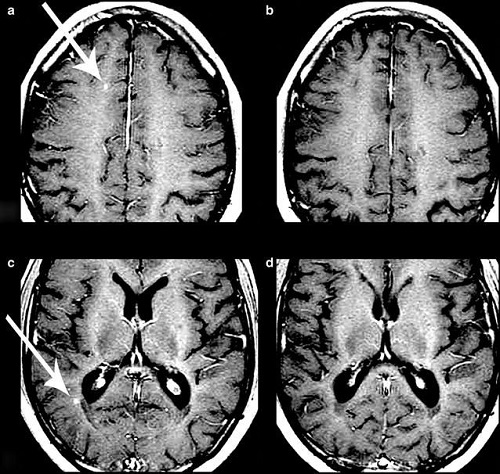

两位患者治疗前后磁共振成像(MRI)的变化

治疗后一年的MRI扫描显示,18名评估患者中有15名无活动性病变,其中1名患者的脑部病变几乎完全消除,研究人员认为,“这是一个特别令人鼓舞的发现”。在这一年中,患者的残疾水平也逐渐获得改善,在没有外力帮助的情况下,步行和工作能力均有所提高。